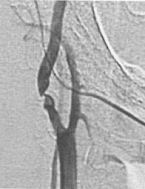

Ангиография – это наиболее точный метод, позволяющий увидеть на экране рентгеновской установки то, что происходит внутри сосуда (рис. 4). С него начинают, если пациент уже перенес инсульт и по данным УЗДГ МАГ выявлены значимо ограничивающие кровоток сужения сосуда, то есть высок риск повторения инсульта. Исследование проводится в специальной операционной, оснащенной ангиографической установкой.

Рис. 4. Критические стенозы внутренней сонной артерии (ангиография).

Во время ангиографии очень тонкий катетер вводится в артерию на ноге и продвигается к сосудам шеи. Место введения катетера будет обработано антисептиком и обезболено. После этого через катетер вводится контрастное вещество, делающее видимыми артерии, питающие мозг, под рентгеновскими лучами. Врач произведет съемку артерии. Если есть стенозы или окклюзии артерий – они будут обнаружены.

Рис. 4. Критические стенозы внутренней сонной артерии (ангиография).Во время ангиографии очень тонкий катетер вводится в артерию на ноге и продвигается к сосудам шеи. Место введения катетера будет обработано антисептиком и обезболено. После этого через катетер вводится контрастное вещество, делающее видимыми артерии, питающие мозг, под рентгеновскими лучами. Врач произведет съемку артерии. Если есть стенозы или окклюзии артерий – они будут обнаружены.